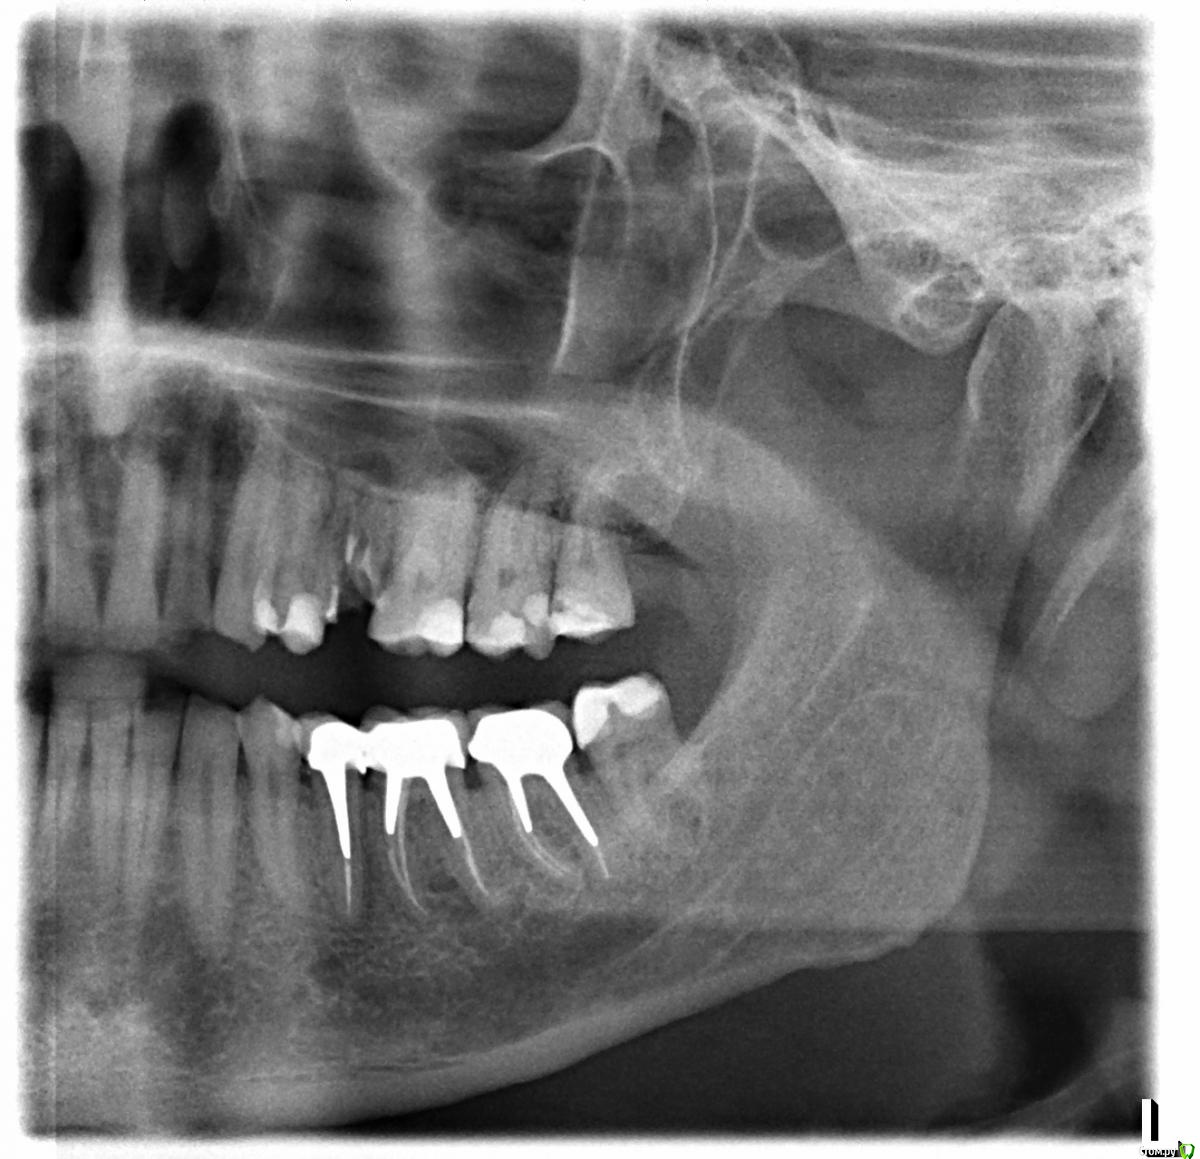

Чертков Александр Опубликовано 14 апреля, 2016 Поделиться Опубликовано 14 апреля, 2016 Согласен с предыдущим комментарием...это бикортикальная фиксацияВот закрытый синуслифт (Спасибо ILGAMSA!!! )http://i075.radikal.ru/1604/6a/fcb066714a5c.jpgСразу послеhttp://s018.radikal.ru/i502/1604/f0/cff497014b21.jpgЧерез три месяцаНа днях установил формирователь... 11 Ссылка на комментарий

alekszander Опубликовано 19 апреля, 2016 Поделиться Опубликовано 19 апреля, 2016 Согласен с предыдущим комментарием...это бикортикальная фиксацияВот закрытый синуслифт (Спасибо ILGAMSA!!! ) Сразу после Через три месяцаНа днях установил формирователь... Саша, а почему не открытый, по срезам вроде там он просился, сколько высоты наращивал? Ссылка на комментарий

Чертков Александр Опубликовано 20 апреля, 2016 Поделиться Опубликовано 20 апреля, 2016 Саша, а почему не открытый, по срезам вроде там он просился, сколько высоты наращивал?Решили начать с закрытого...пожелание пациента...все получилось По высоте там видно, в среднем на 5-6 мм подняли Ссылка на комментарий

Чертков Александр Опубликовано 21 апреля, 2016 Поделиться Опубликовано 21 апреля, 2016 Можно снимок "до" и на снимке "после"сместить курсор дистальнее на 2 мм. (Я не привязываюсь. Хочу разобраться,чтобы в перспективе планировать. Есть мысль:когда "подбиваешь" дно нарастает сколько необходимо и апекс покрыт кортикалкой,если мягко поднять- мембрана "обвисает" на апексе и нарастает не более 3мм).http://s010.radikal.ru/i312/1604/ec/5c9cacf33ca2.jpghttp://s019.radikal.ru/i624/1604/2d/6b259ffd5f86.jpgТак? 4 Ссылка на комментарий